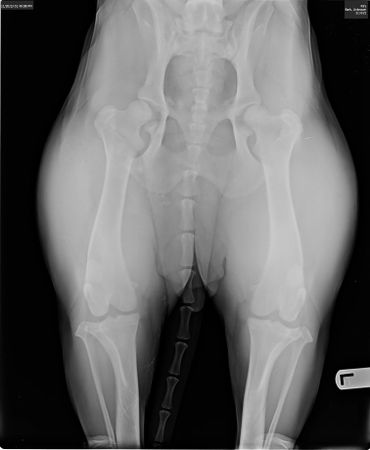

OFA

Elbow: Grade 1

Hips: Mild subluxation